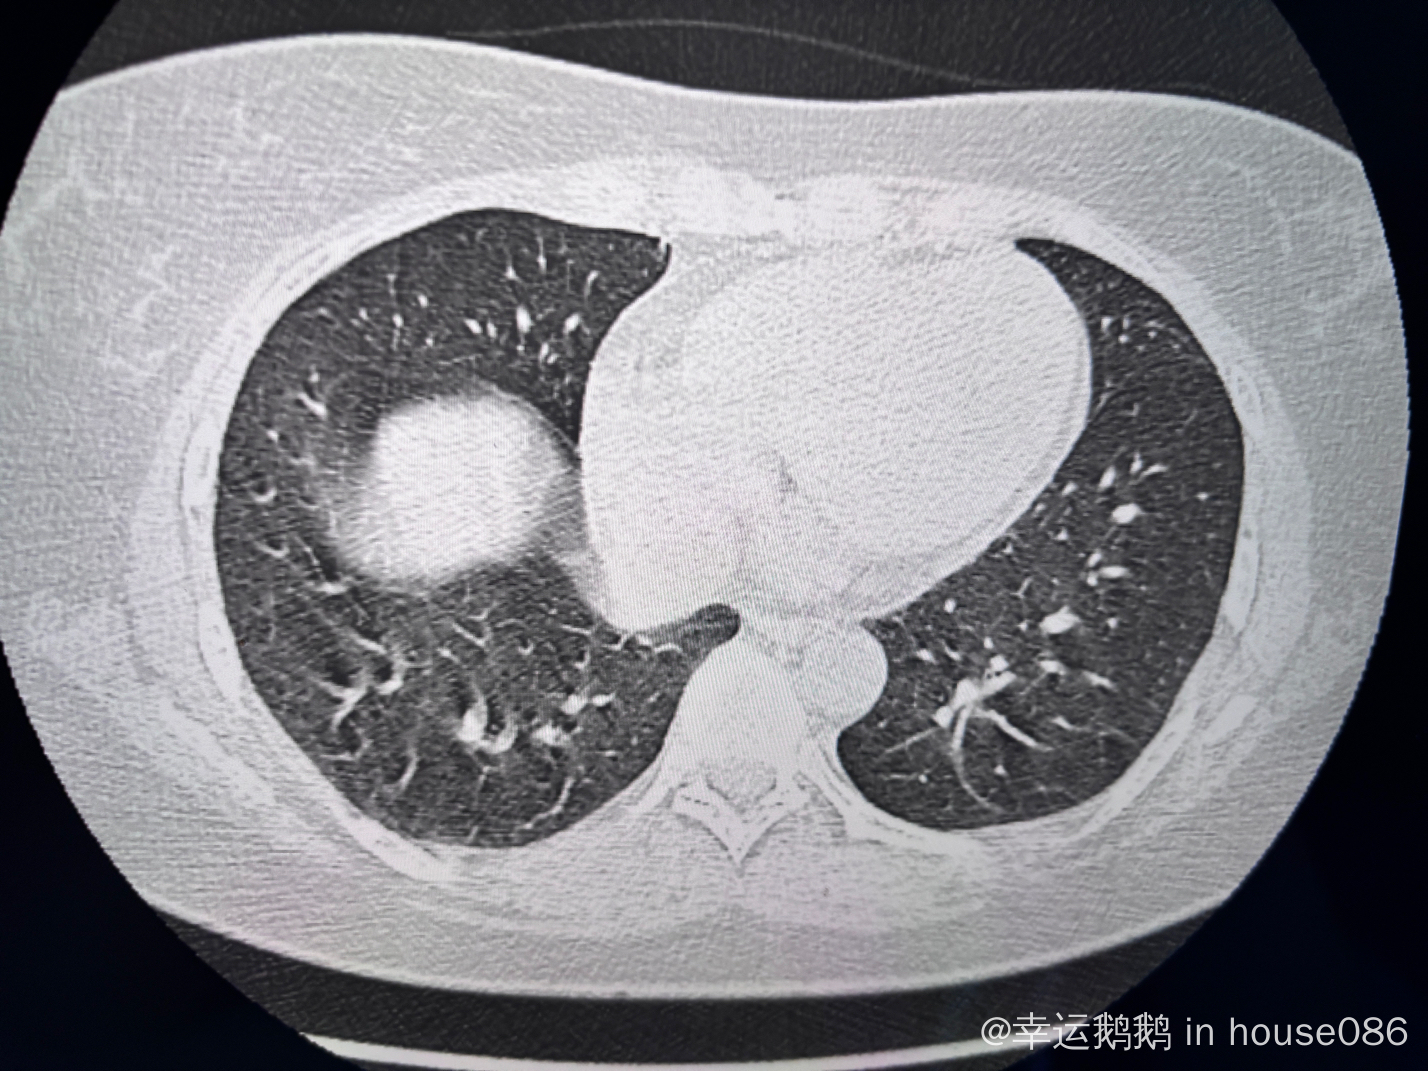

上午刚做的petCT, 还没出报告,请问这个肺像是间质性肺炎吗?

请问下各位大佬这个肺是不是像间质性肺炎表现? 万分感谢!

之前我见过其他人的图像,典型特征是那种蜂窝状、毛玻璃样的阴影,只能说你发的这个图像看着不太像,我觉得还要结合一些症状,比如咳嗽,呼吸气短啥的,还是尽快跟医生联系综合的看一下比较妥